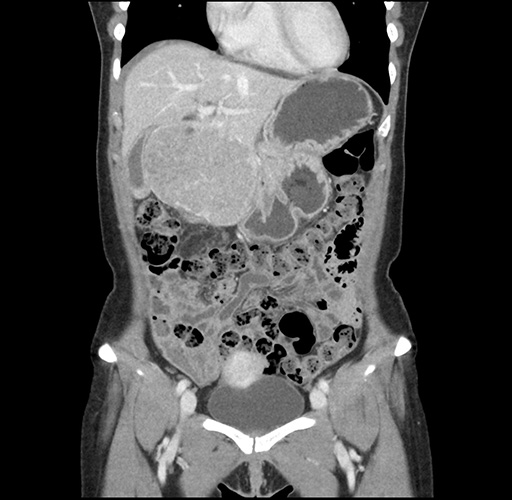

Imaging Analysis

Look through the patient's CT scan to identify any areas of concern for the necessary procedure.

Based on your CT findings, which issue(s) would give reason for "planned slowing down moment(s)" in this case?